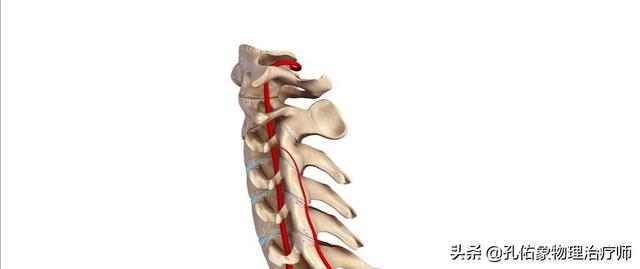

4.椎动脉型颈椎病

其发病率也低,主要就是椎动脉受到卡压或是椎动脉迂曲,狭窄或是痉挛,造成椎-基底动脉供血不全,常常因为颈部的旋转而诱发。这类型的颈椎病也可以通过保守治疗取得疗效。